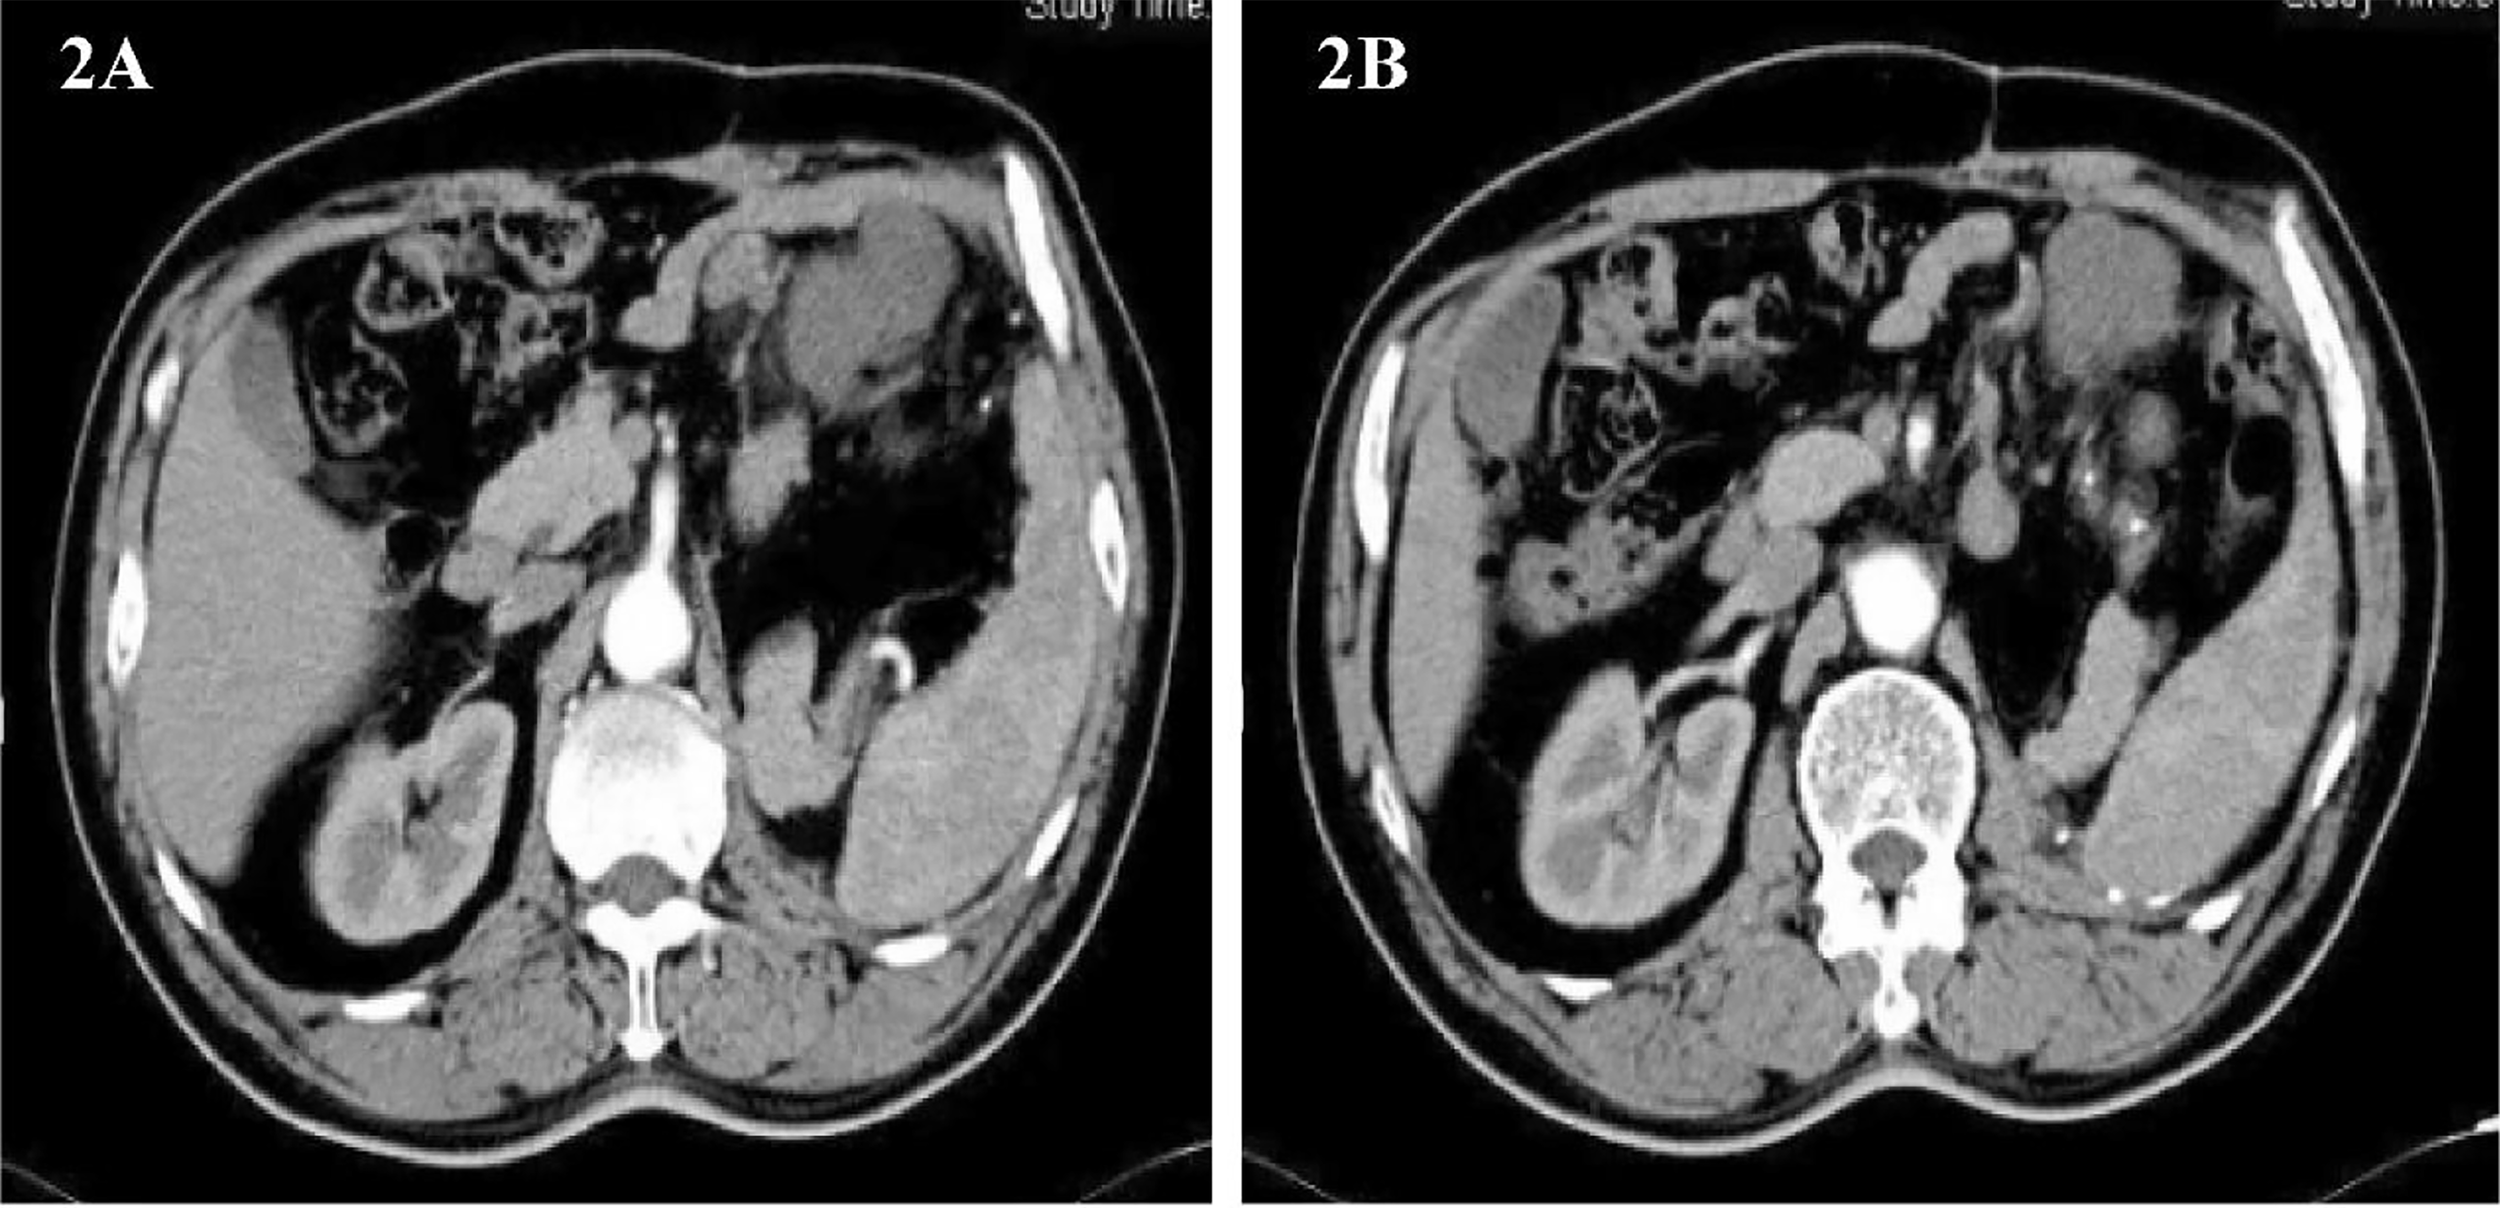

Imaging follow-up found that the tumor recurred, and it has been less than 1 year since the patient’s last surgery. Abdominal CT showed a round, slightly low-density foci in the upper left abdominal cavity with enlarged adjacent lymph nodes(Figures 2A, B). The patient was soon admitted to the hospital for surgery for the second time. On February 22, 2013, the same surgical team performed a combined organ resection for the patient. Operation name: Abdominal tumor resection + partial resection of small intestine. The postoperative pathology was dedifferentiated liposarcoma, and the dedifferentiated components were like myxofibrosarcoma. Immunohistochemistry : CD34(+), Caldesmon(+), SMA(+), CD117(-), Dog-1(-), S-100(-). The Ki67 positive rate is about 30%. The patient’s gastrointestinal motility recovered on the third postoperative day, and the diet gradually transitioned from a liquid diet to a normal diet. The patient was discharged from the hospital on March 1, 2013.

Figure 2

(A, B) Abdominal image before the second operation.